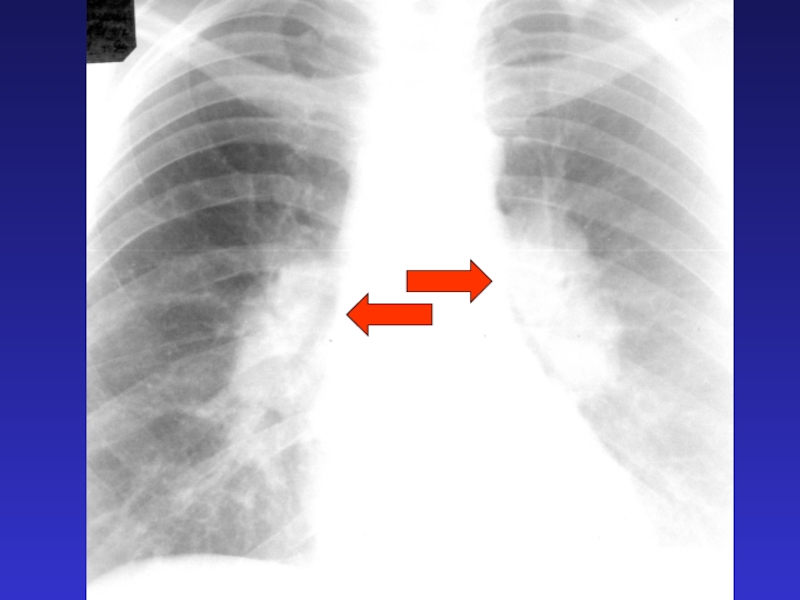

Слайд 83Синдром патологии

корня легкого -

неструктурность и расширение корня легкого

Синдром патологии корня легкого -неструктурность и расширение корня легкого

Слайд 84Причины патологии корня

- увеличение лимфатических узлов - лимфаденопатия

- нарушение

гемодинамики – ЛВГ и ЛАГ

Причины патологии корня - увеличение лимфатических 	узлов - лимфаденопатия- нарушение гемодинамики – 	ЛВГ и ЛАГ

Слайд 88Расширение легочной артерии

Расширение легочной артерии